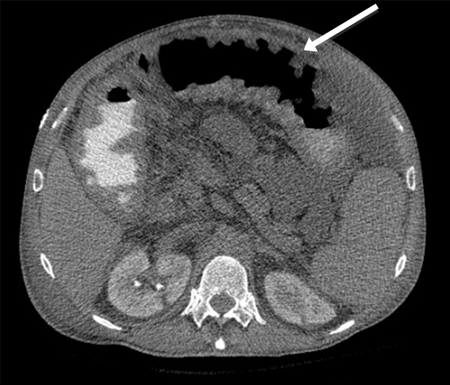

A TC fornece evidências da extensão do comprometimento intestinal decorrente da isquemia; ela é útil para diagnosticar isquemia mesentérica aguda, mas os achados podem ser inespecíficos na isquemia inicial.[39][40] Os primeiros sinais incluem espessamento da parede intestinal e dilatação luminal. Os sinais tardios incluem pneumatose (gás na parede intestinal) e gás mesentérico ou venoso portal, o que geralmente indica necrose intestinal.[32][41] Os outros sinais tardios incluem um intestino edematoso e um aumento variável do intestino cercado por líquido livre.[31] Pode mostrar espessamento da parede intestinal com sinais de impressão digital sugestivos de edema ou hemorragia submucosos, o que sugere um pior prognóstico.

[Figure caption and citation for the preceding image starts]: Tomografia computadorizada (TC): espessamento colônico com pneumatose intestinalDo acervo da Dra. Jennifer Holder-Murray; usado com permissão [Citation ends].

[Figure caption and citation for the preceding image starts]: Homem de 84 anos que apresenta sintomas sugestivos de doença intestinal isquêmica: (A) Tomografia computadorizada (TC) abdominal que revela uma formação de ar circunferencial maciça e em forma de faixas como pneumatose intestinal (setas) e edema pronunciado da gordura mesentérica (ponta de seta) ao redor das alças intestinais necrosadas; (B) Outra secção da TC abdominal mostrando pneumatose segmentar longa do intestino delgadoLin I, Chang W, Shih S, et al. Bedside echogram in ischaemic bowel. BMJ Case Reports 2009:bcr.2007.053462 [Citation ends].